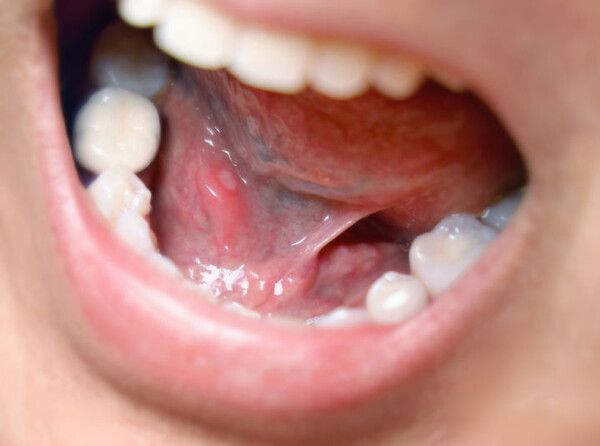

사진 = 뉴시스

입안 염증과 잇몸 질환 완화에 '숭늉'이 효과적이라는 전문가 의견이 나왔다.

그는 "입안은 녹이 가장 많이 쌓여있는 곳으로, 우리 몸의 만성 염증 중 약 80%는 잇몸 질환과 관련이 있다"며 "숭늉이 이러한 염증을 완화하는 데 효과적"이라고 말했다. 실제로 심한 잇몸 염증으로 고생하던 70대 여성이 숭늉을 꾸준히 섭취한 결과, 한 달도 채 되지 않아 통증과 염증이 크게 줄어든 사례를 소개하기도 했다.